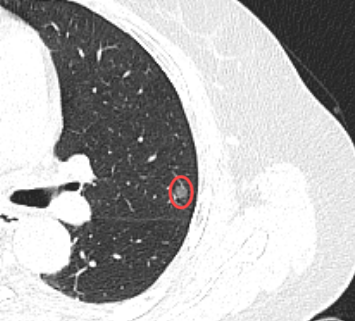

患者王阿姨在体检中发现左肺高危结节,经我院呼吸科"肺结节精准评估门诊"初步筛查,考虑恶性可能大。呼吸科团队立即启动多学科联动机制,联合胸外科、影像科、病理科进行会诊。

肺结节≠肺癌,但高危结节需警惕!对于具有分叶征、毛刺征等影像学特征的结节,建议尽早就诊。我院建立的肺结节全程化管理体系,能有效避免漏诊误诊,为患者争取最佳治疗时机。